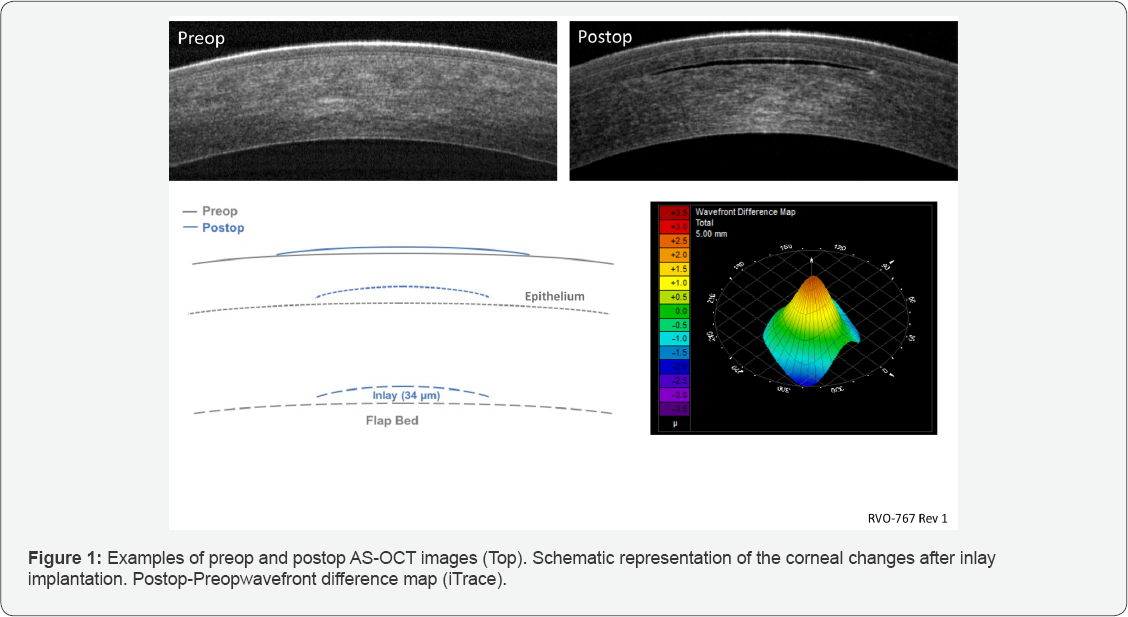

The corneal structural changes that occur after Raindrop Inlay implantation was deduced in a study by utilization of anterior segment optical coherence tomography (AS-OCT) to measure changes in anterior stromal elevation and epithelial thickness (Figure 1, top) and wavefront measurements to measure the change in total anterior corneal surface (Figure 1, bottom right) [4]. The inlay's volume raises the anterior stroma which is demonstrated by a change to the shape of Bowman's layer. The anterior stromal thickness change above the inlay was shown to be ~28 |im on average (Table 1), which is only ~85% of the inlay’s central thickness (Figure 1). The 28 |im rise in the anterior stroma lifts the overlying epithelium, resulting in central epithelium thinning by ~18 |im (Table 1). This epithelial thinning tapers out peripheral to the inlay diameter, leading to slight peripheral thickening, not measurable by AS-OCT. The resulting anterior elevation change to the central cornea was ~10 |im (the difference in 28 |im anterior stroma thickness change and 18 |im epithelial thinning) (Figure 1, Table 1), which gradually reduces to zero as the epithelium redistributes to about twice the inlay diameter. This steady change in corneal surface height creates the inlay-induced central steepening power profile resulting in 4.3 D add power induced at the center [3,4].